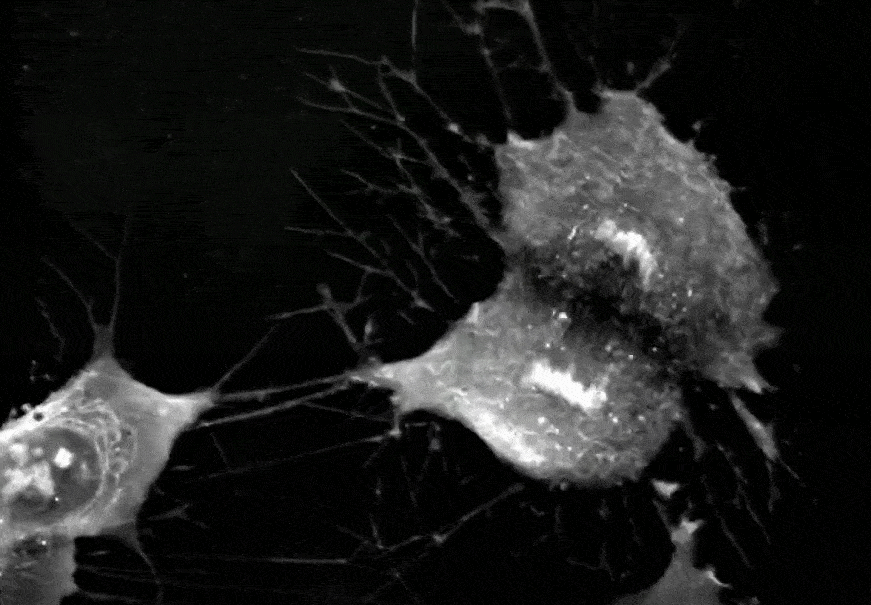

MSC衰老后胞体会增大,增殖能力减弱

间充质干细胞正在进行分裂增殖